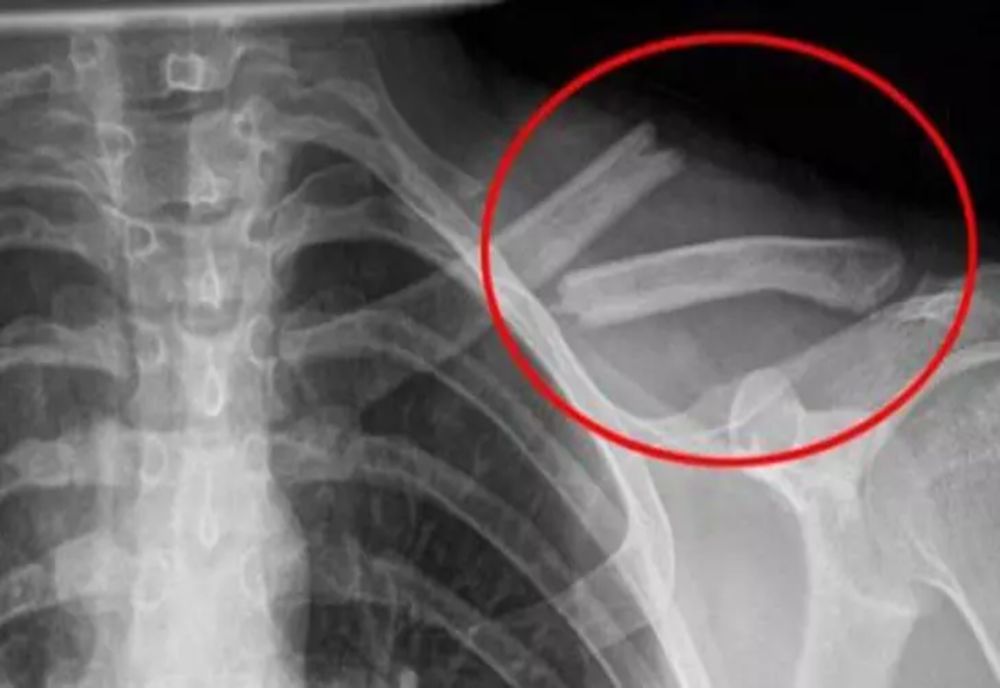

După 60 de minute - Toate mineralele care ar trebui să ajungă în oase, inclusiv magneziul, calciul şi zincul, sunt excretate în urină.

Consumul de băuturi acidulate duce la distrugerea oaselor pe termen lung.